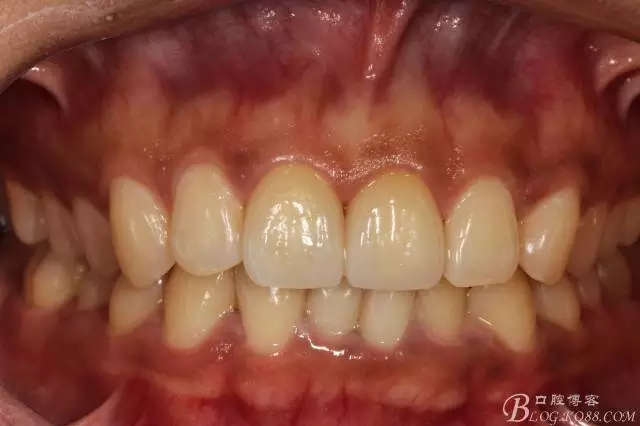

2016年1月復(fù)查邊緣已不行了,改做瓷貼面,修復(fù)完成后對(duì)比前后效果明顯。

看圖吧——

2016.1復(fù)查情況很不好,再次建議做瓷貼面并告知各自優(yōu)缺點(diǎn)。這回患者同意并選擇鑄瓷貼面。